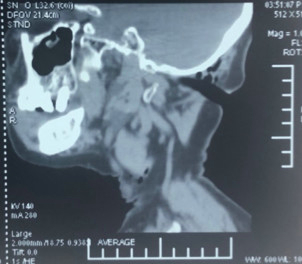

急查头部CT显示这段树枝直接嵌入在枕颈交界区,毗邻最重要的结构——颈髓和椎动脉旁。通常这个位置是手术风险极高的区域,稍有不慎动脉出血可能是致命性的,颈髓损伤也可能会出现终身瘫痪残疾,凶险程度可见一斑。

CT显示树枝位于颈枕交界区,寰椎后弓有骨折,毗邻椎动脉管